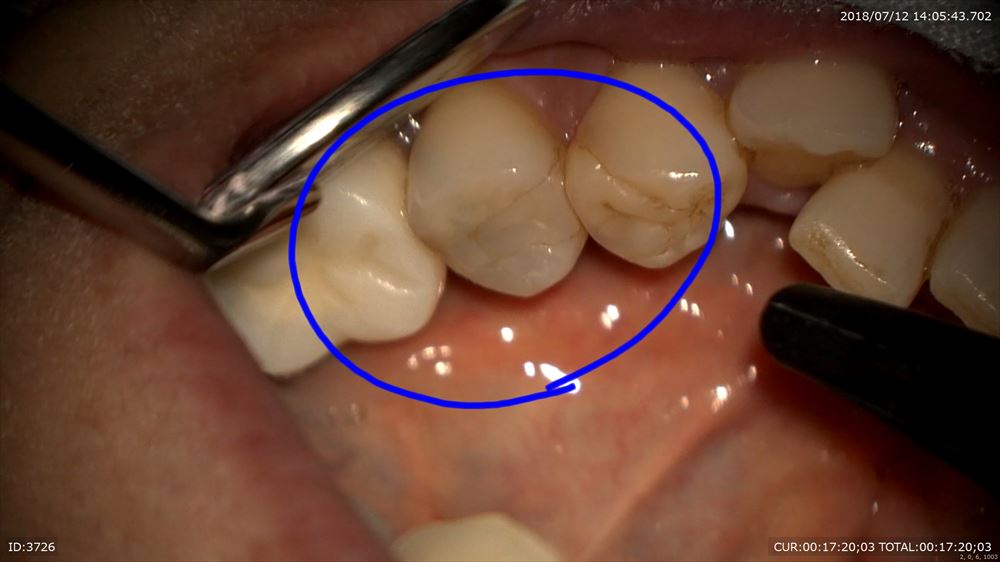

歯科ドックで左下の根管治療の不備とその手前に通常のレントゲンには映りにくい場所の虫歯をCTで発見しました。

ここに肉眼では虫歯があるなんて思いませんよね。

ほらCTとマイクロスコープを使用すると。。

CTにはしっかり写っていました。歯科ドックは大切。